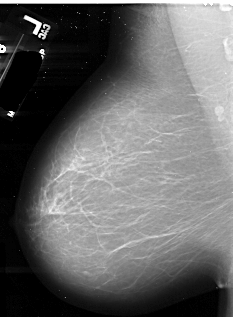

A_1075_1.LEFT_MLO

LEFT_MLO LINES 6016 PIXELS_PER_LINE 4411 BITS_PER_PIXEL 16 RESOLUTION 42 NON_OVERLAY